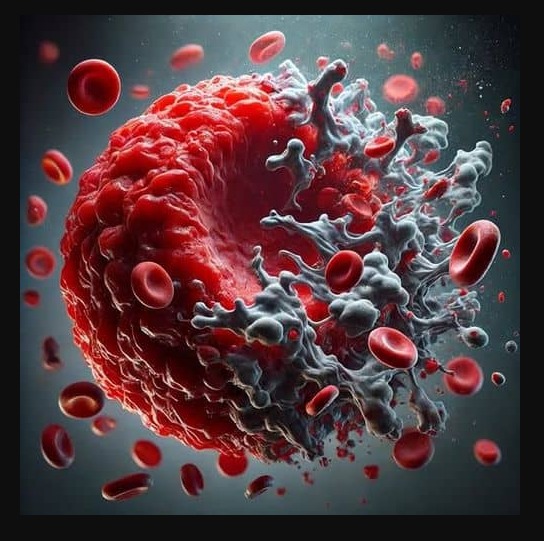

Eine Infektion mit SARS-CoV-2 kann zu Long- und Post-Covid – Symptomen führen. Die Zellen der roten Blutkörperchen sind für den Transport von Sauerstoff zu den Organen verantwortlich. Mit Elenant® kann die Sauerstoffaufnahme wieder unterstützt werden. Sie werden beschädigt und verlieren einen Teil ihrer Funktion. In der Folge erreicht weniger Sauerstoff die Organe und der Energiehaushalt wird nachhaltig gestört. Betroffene fühlen sich antriebslos und erschöpft. Die zerstörten Reste der roten Blutkörperchen sausen nun als lineare Proteine (Spikes) durch alle Arterien, Wenn Sie dann die feinsten Kapillaren verstopfen, werden auch die betroffenen Organe mit zu wenig Sauerstoff versorgt. Dieser niedrige Sauerstofflevel ist charakteristisch für all die bekannten Long-Covid Symptome und erklärt viele Symptome wie Müdigkeit, Schwäche und Konzentrationsprobleme. Das Blut wird in einen Fluss der Schwäche verwandelt.

- Covid-Infektions-Reste zersetzen die roten Blutkörperchen

- Dadurch gelangt weniger Sauerstoff in die Organe

- Die Folge ist ein niedriger Energie-Level

Foto: UV-Licht Mikroskop

Blutbild voll Spikes nach diversen Covidinfektionen und 3x geimpft

Aufgenommen August 2025

Während und nach einer Behandlung mit herkömmlichen Methoden

(Sauerstoff, Nährstoffe, Blutaustausch)

Foto: UV-Licht Mikroskop

Blutbild nach 6 Wochen Behandlung mit Sauerstoff und Nährstoffen

Es sind einzelne Blutzellen erkennbar, es sind allerdings auch weiterhin Spikes im Blut

Aufgenommen Ende Sept. 2025

- Weniger Spikes im Blut

- Einige klar abgesetzte Blutkörperchen

- Keine nachhaltige 100% Ausleitung der Spikes (lineare Tromben)

- Besserung der Sauerstoff / Energieversorgung des Körpers

- Weiterhin zu wenig Sauerstoff im Blut für ein aktives Leben